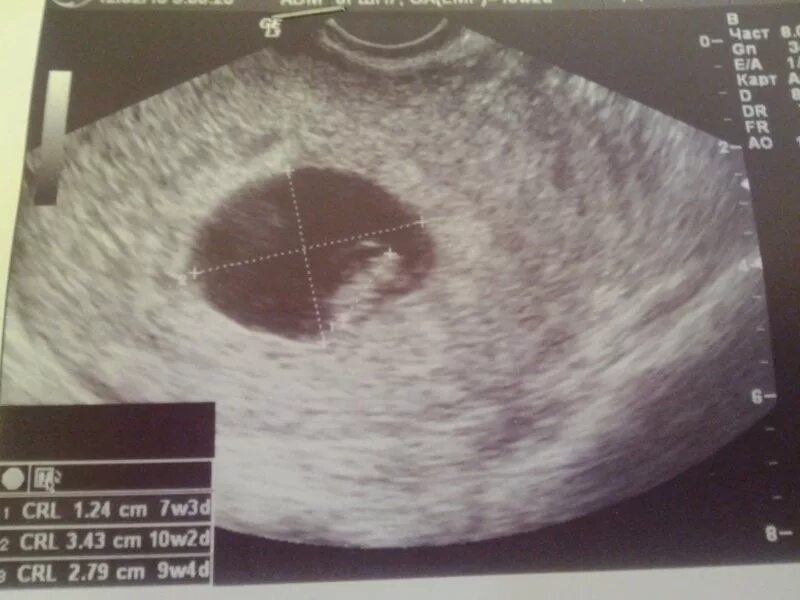

Желточный мешок 2 мм